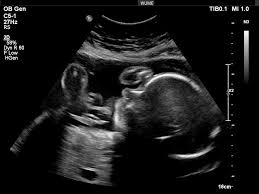

During the 120 ish-day window when your eggs are undergoing the final maturation process there is much you can do to improve your fertility success. ‘Making Babies’ Preconception Care Program is all about maximising the ‘fertility-optimising ‘ window.

Read MoreThe health of eggs in a woman’s ovaries influences so much – regularity of menstrual cycle, future fertility and ability to conceive. It is good to know that recent research has proven that a woman’s eggs for life is not a finite number. Stem cells in the ovaries are capable of growing new eggs during the reproductive years.

Read MoreHave you ever wondered about the benefits of a preconception care program? There are so many, from ease of conception, pregnancy and delivery - to knowing you are giving your baby the best chance of a healthy start to life.